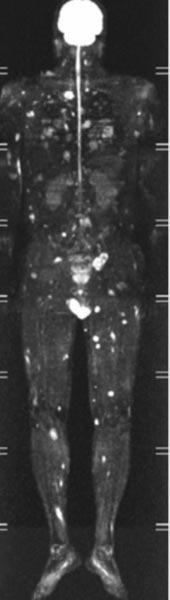

Tum Vucut Mr Check Up Hayat Ta Olay Gazetesi Bursa

Tum Vucut Mr Check Up Hayat Ta Olay Gazetesi Bursa

Tum Vucut Mr Check Up Hayat Ta Olay Gazetesi Bursa

Tum Vucut Mr Check Up Hayat Ta Olay Gazetesi Bursa